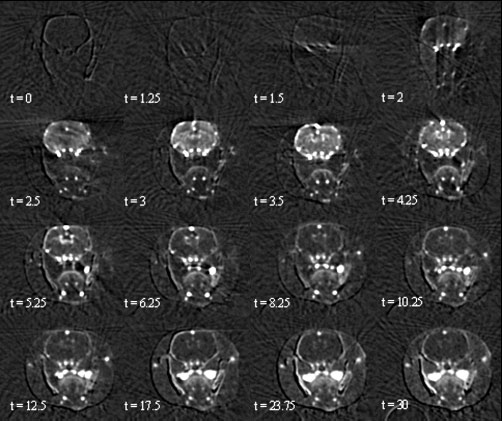

Fig. 97: Head axial time course of iodine concentration maps (mg mL-1) on a healthy rat obtained by SRCT, after a bolus infusion (only 16 images amongst 125 are displayed). Time (t) is expressed in s, the infusion starts at t = 0. Iodine enters the brain vasculature via the arterial inputs, passes through the brain microvasculature and is washed out by the intracerebral and extracerebral venous outputs. |

The experiments are performed on healthy rats. After the intravenous injection of a bolus of an iodinated contrast agent, Computed Tomography (CT) images are acquired every 2 seconds. The first image acquired before iodine infusion is subtracted from the others in order to get CT slices expressed in absolute iodine concentrations (Figure 97). Each pixel of the slice provides a curve representing the iodine time course in the corresponding brain voxel. These curves are fitted by gamma-variate functions in order to avoid the recirculation phenomenon. CBV and CBF maps (Figure 98a and b) are then computed by using these fits in the tracer kinetics models. A correction for partial volume effects in the chosen arterial input is necessary for a good quantification. Mean CBV and CBF values (n = 7) are found equal to 2.1 mL 100 g-1 ± 0.38 and 129 mL 100 g-1 min-1 ± 18 in the parietal cortex; 1.92 mL 100 g-1 ± 0.32 and 125 mL 100 g-1 min-1 ± 17 in the caudate putamen. These values are in good agreement with the reported ones in the literature.